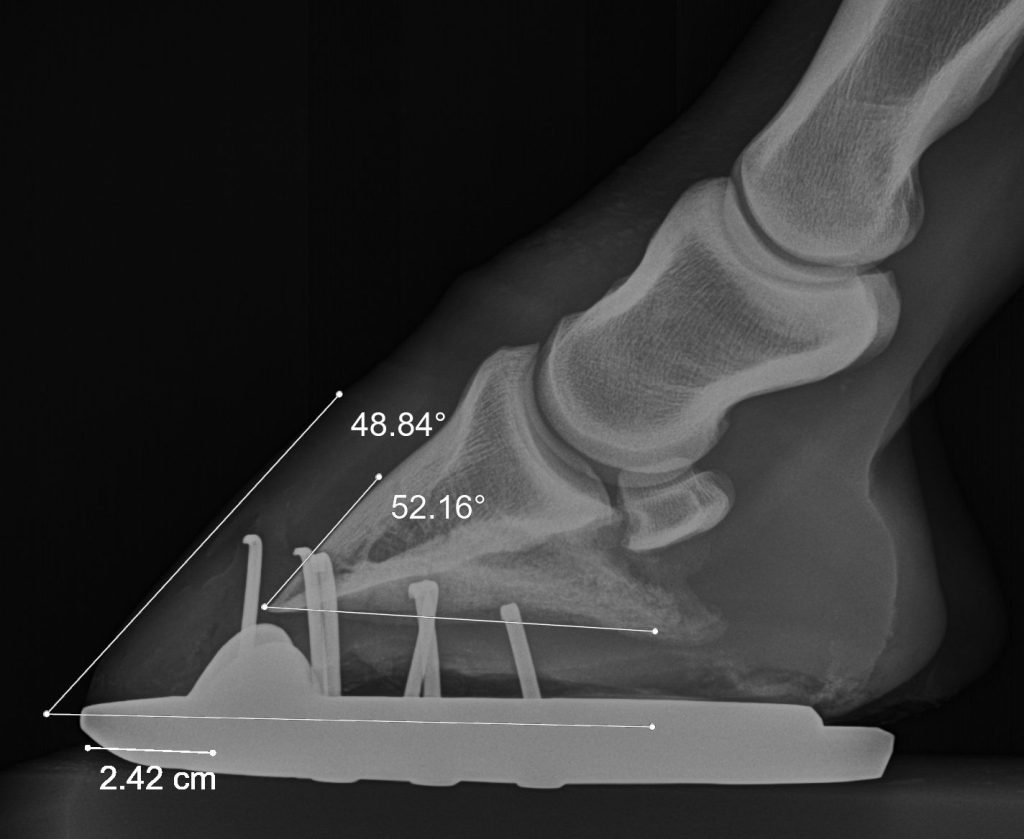

As you can see in the x-ray, he was pretty darn negative in his right hind. His left hind was just barely negative—less than a degree—but either way, this was it. This was the answer we had been searching for. This was the answer for why my horse, who has no glaring conformational flaws to speak of aside from pasterns that are a little too long in the front, who has no kissing spine or neck arthritis or any bony changes anywhere that we’ve looked, has had chronic suspensory issues (which were worse on the right side) and soreness in his SI and back and withers for pretty much the entire time I’ve owned him. I treated the symptoms—he got regular chiro work to keep his back more comfortable, and I did his carrot stretches religiously—but it’s no wonder that we never solved the problem. It’s no wonder that he had such a hard time lifting his back and using himself properly, even though he really did try. He was literally set up for failure from the beginning.

Luckily for me, our farrier was there for one of our barn’s regular Monday visits, so he came over when he had a break between shoes and looked at the x-rays with our vet, and they came up with a game plan on the spot. We weren’t going to take Cooper’s shoes off that day—he was halfway through his cycle and due two weeks later—but the next time his feet were done, he was getting wedge pads with full frog support on both hind feet to lift his heels and get the strain off of his suspensories so that we didn’t reinjure them. In the meantime, I had my own instructions: trot and trot and trot and trot.

There’s still a good bit left for us to do at this point. In a few vet visits, we’ll take new farrier films of his hind feet to see how they’re doing (and see if he’s improved enough that we can drop him down to a lower wedge). I’ve made the executive decision that I’m going to treat him for ulcers because he’s been pretty grumpy about having his girth done up and has been way spookier than usual over the last couple of months, and it would hardly be surprising if he did develop them after all the medications and stall rest and stress of the last six months, so we’ll most likely be starting that in a couple of weeks once I get the omeprazole. We’re still working on fixing the canter under saddle and that’s going to be a continual process of strengthening him and continuing to retrain his muscle memory (although he was way better today—I swapped him over to a double-jointed baucher rather than the loose-ring nathe, and he was way more responsive and less stuck with the baucher action even on the left lead).

If I could pass one piece of advice on to everyone as a result of this whole adventure, it would be this: start with the feet. I probably still would’ve had to spend almost all the money that I’ve spent even if I’d x-rayed his feet a year ago, because we needed to quiet his body down to let him get comfortable again, but I could’ve paid a couple hundred dollars a hell of a lot sooner to have the answer to pretty much every question that I’ve had about him over the last (almost) five years. I just didn’t know to ask until my dear friend eventingenzo clued me in to NPA and what it can cause over the last year or so. Worst case scenario, you take the films and you’re out a couple/few hundred bucks to find out that there’s nothing wrong, but you might also take them, find out your horse is negative, and avoid potentially thousands of dollars of diagnostics and treatments trying to repeatedly treat things that are actually symptoms, not the cause. Cooper will be getting (at least) annual films from now on, and so will any other horse I have.